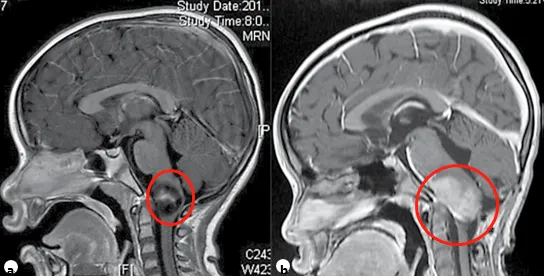

毛细胞星形细胞瘤是儿童年龄组中常见的神经胶质瘤亚型,主要发生于幼儿(中位年龄为4岁)。PA在后颅窝、视神经通路、背侧外生性脑干肿瘤中占比较大,在T1加权磁共振成像上通常表现为低信号的囊性肿块,其强化部分显示明亮增强(见图1)。

图1:患儿术前(a)与术后(b)颅脑磁共振成像对比。术前影像显示右侧丘脑区域存在巨大囊实性占位,提示胶质瘤可能,可见皮质脊髓束(负责人体肢体运动的神经传导束)受压及脑室扩大。术后影像证实肿瘤已实现全切,脑组织复位良好,未见脑出血、脑水肿等手术损伤征象。